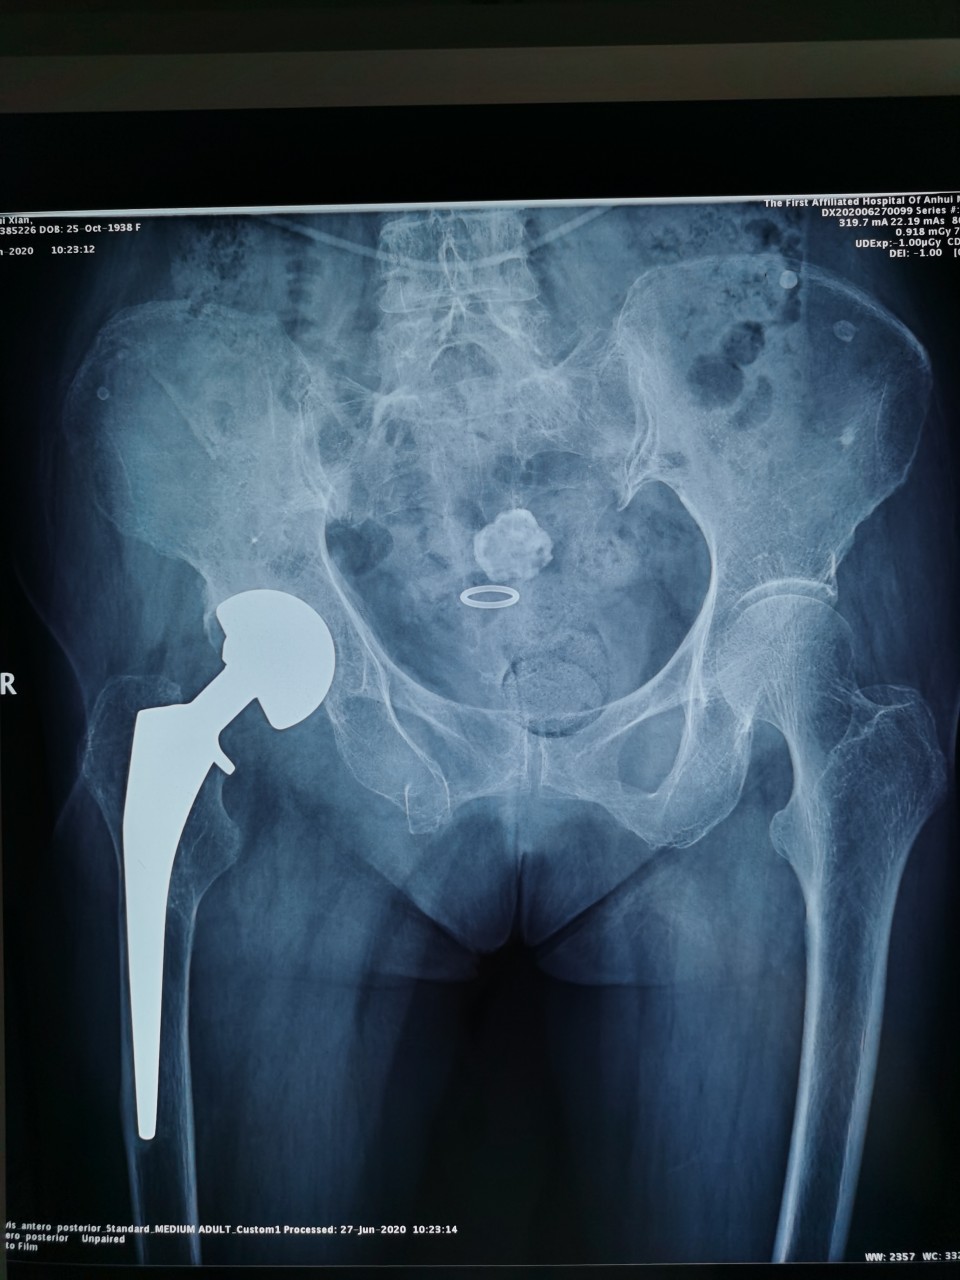

术前

患者女,81岁,既往曾因股骨颈骨折行右髋关节置换术,此次入院当天因外伤致髋部周围疼痛及活动受限入住我院创伤骨科。经术前检查及评估,诊断为“骨盆骨折”。对于此例高龄骨盆骨折患者,王刚副主任医师团队决定为其施行“闭合复位微创内固定手术”,手术用时仅30分钟,在闭合复位后,通过3枚骨盆通道螺钉固定骨折部位,基本无手术出血,术后两天患者恢复良好,予以出院。